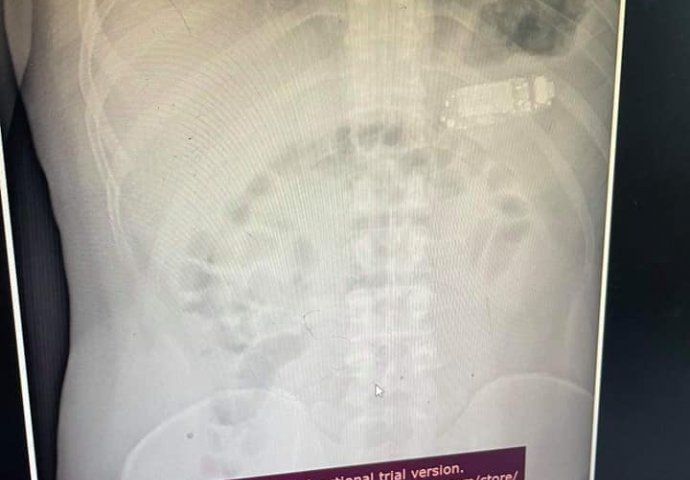

Neobična intervencija dogodila se na Gastroenterološkoj klinici u Prištini, prilikom koje je iz stomaka muškarca (33) izvađen mobilni telefon, koji je progutao prije četiri dana, javlja RTS.

Ljekar Skender Teljaku predvodio je medicinski tim tokom zahvata, rekavši da su prvo izvukli maske sa telefona iz trbuha, a zatim i bateriju, koja se smatra najopasnijim dijelom.

„Osoba koja je progutala strano tijelo, morala je hitno na gastroskopiju. Kada smo ušli u stomak vidjeli smo da je telefon podijeljen na tri dijela. Jedan dio je bio plastični prednji i zadnji poklopac, plus baterija unutra. Ušli smo opremom koju imamo. Na kraju smo izvadili bateriju, koja je od svih ovih dijelova najopasnija jer je taj dio ozračen i mogao je da eksplodira u crijevima, da oslobodi hemikalije“, rekao je doktor Teljeku prištinskim medijima.

Zahvat je trajao dva sata, bez presijecanja stomaka, prenosi RTS.